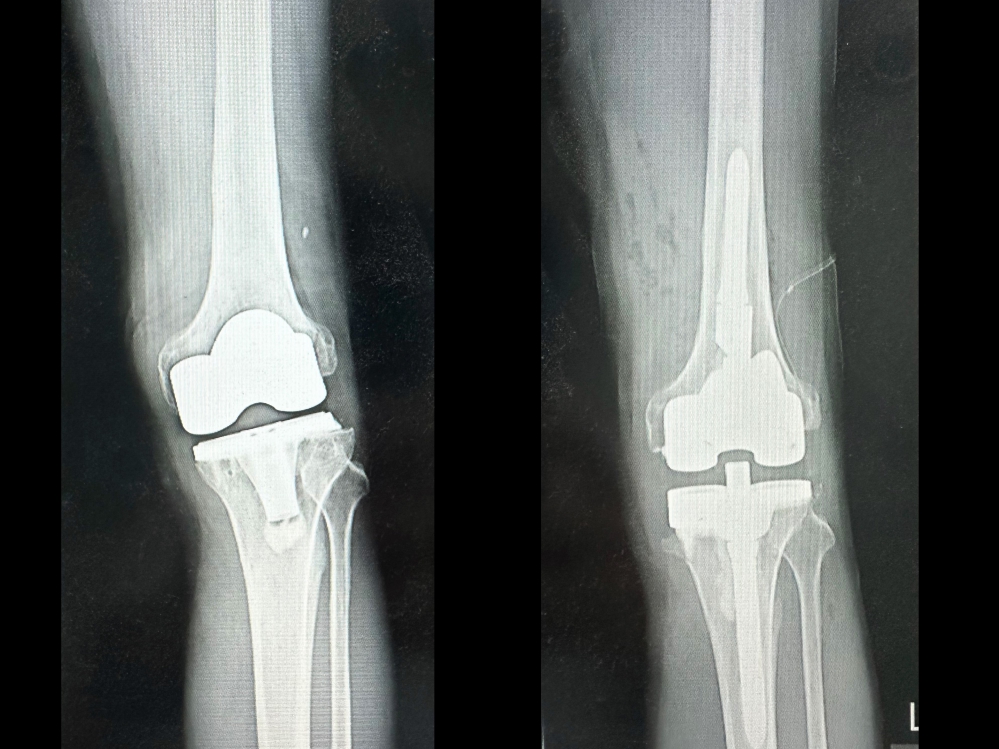

林先生經由親友介紹,轉到台中慈濟醫院趙子鎔醫師門診檢查。X光與電腦斷層顯示,原本置換的人工關節角度出現偏差,導致膝關節軸向錯位、受力不均。趙醫師表示,人工關節應與人體重心軸線垂直,但病人術後角度卻反向歪了約十度,造成走路一踩就歪,膝蓋反覆發炎積水而疼痛。

趙子鎔醫師與林先生反覆分析溝通後,進行「人工關節翻修再置換」手術,透過電腦斷層影像規劃,重新調整關節角度與力學軸線。術後第二天,林先生便能下床行走,一個月後腫脹消退,不再反覆積水,已經能獨自行動,甚至可以搭公車回診。他開心表示:「不再腫、不再痛,走路終於又有力量,非常感謝趙醫師。」